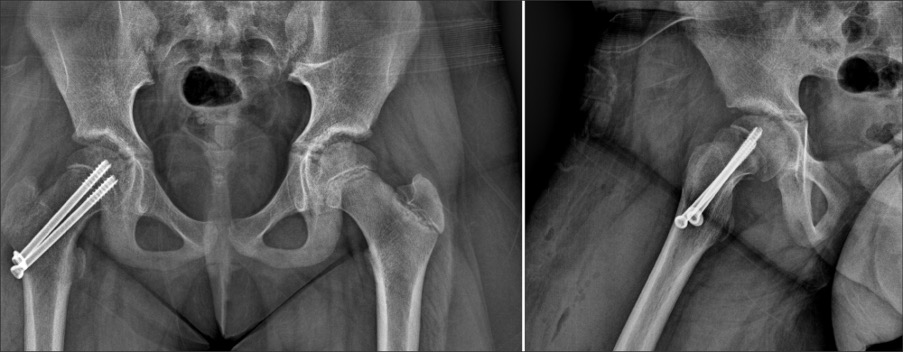

대퇴골두 골단 분리증

(SCFE)

수술적 치료

· 성장판이 닫히기 전, 성장판을 관통해 대퇴골두까지 나사못을 삽입하여 더 이상의 어긋남을 방지합니다.

· 성장판이 닫힌 후, 대퇴골두가 어긋난 경우 뼈 수술을 통해 교정합니다.